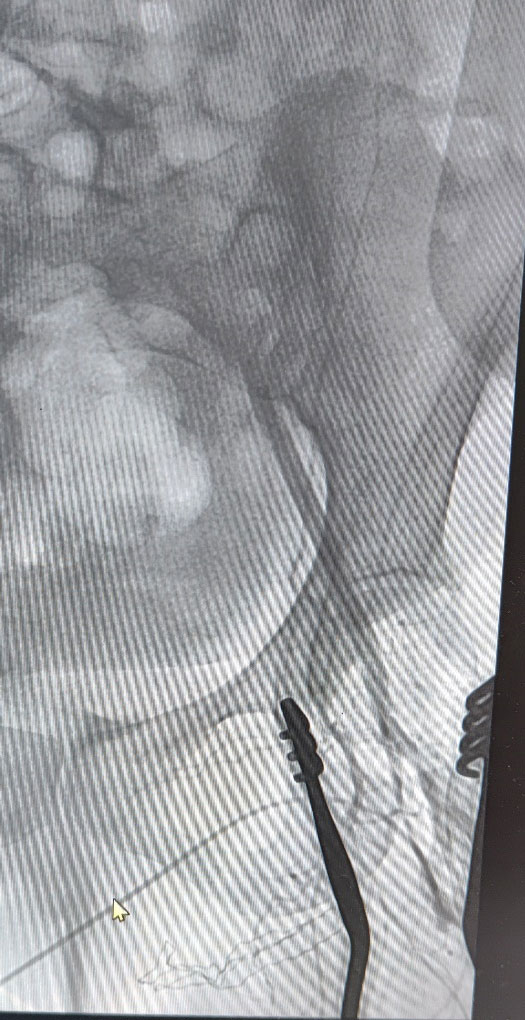

She underwent emergency left transfemoral thrombectomy and puncture angiogram of the left iliac artery at the hybrid cath suite. Chronic thrombus was retrieved from the iliac and femoral artery and evidence of a proximal (iliac) occlusion was seen in the angiogram. It was akin to keeping a sinking ship afloat as she kept thrombosing again and again on table even after multiple thrombectomies. Further attempts were stopped, and she was maintained on high dose IV anticoagulation while investigations were done to deduce a cause for thrombophilia. She was found to have thrombocytosis. Her cardiac system was normal and there was no source of emboli upstream. The left leg developed progressive gangrene, and she had to undergo a below knee amputation of her left leg.

Intraop Angiogram Shows Sudden Cut-off at External Iliac Artery